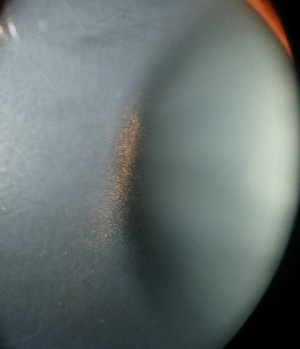

Pigmentary glaucoma is a type of secondary open-angle glaucoma characterized by heavy homogenous pigmentation of the trabecular meshwork, iris transillumination defects, and pigment along the corneal endothelium known as the Krukenberg spindle (Image 1). Pigment dispersion syndrome is used to classify individuals who exhibit these features but who have not progressed to optic nerve damage and/or visual field loss (signifiers of PG), even if the IOP is elevated.

Cornea. The posterior surface of the central cornea should be carefully examined for the presence of pigment.

This pigment is often arranged in a the shape of a Krukenberg spindle, a narrow or rounded oval of brown pigment, usually 0.5–2.5 mm wide and 2–6 mm in length, vertically oriented due to convection currents. Pigment is typically densest at the center, thinning out at the edges to form a spindle-like shape.[41] Krukenberg spindles are present in roughly 90% of patients with PDS or PG. Whether dense or very fine granules of pigment are present, visual acuity is not reported to be affected. Corneas with PDS or PG are also no thicker than normal corneas and have not been reported to have decreased endothelial cell counts.[42]